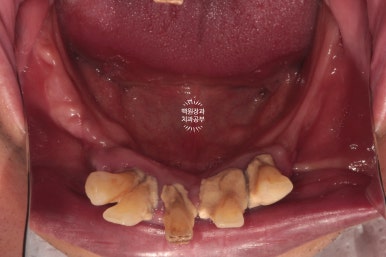

교합면에서 촬영한 사진입니다.

치아를 다 발치해야겠다는 생각이 절로 드는 환경이셨어요.

혹시나 보이시나 모르겠지만, 상당히 잇몸뼈가 얇음이.. 예상되는 상태였습니다.